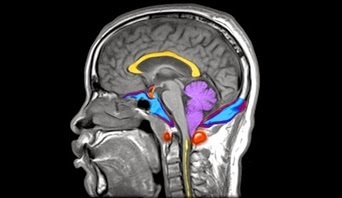

new meets old or vice versa

By now, the neurologist and I had been thinking about Arnold Chiari malformation which means the bone at the top of the spine is a bit wonky so bits of the brain start to slid down the spinal canal. As you can imagine, that is a wee tad sore.

Went to Gp and got stuff to stick up my nose as soon as the headache starts. This medicine works very well but gave no clue as to what was causing the pain. He diagnosed cluster headache, often called the suicide headache because it is that painful. I am lucky that, with me, the pain is there and gone within thirty minutes and (so far) it is always in the small hours of the morning. But I can’t imagine living with that pain four or five times a day. If a patient does, the current treatment of choice is a having a brain stimulator surgically placed in the deep part in the brain to derail the signals.

By now, the neurologist and I had been thinking about Arnold Chiari malformation which means the bone at the top of the spine is a bit wonky so bits of the brain start to slid down the spinal canal. As you can imagine, that is a wee tad sore.